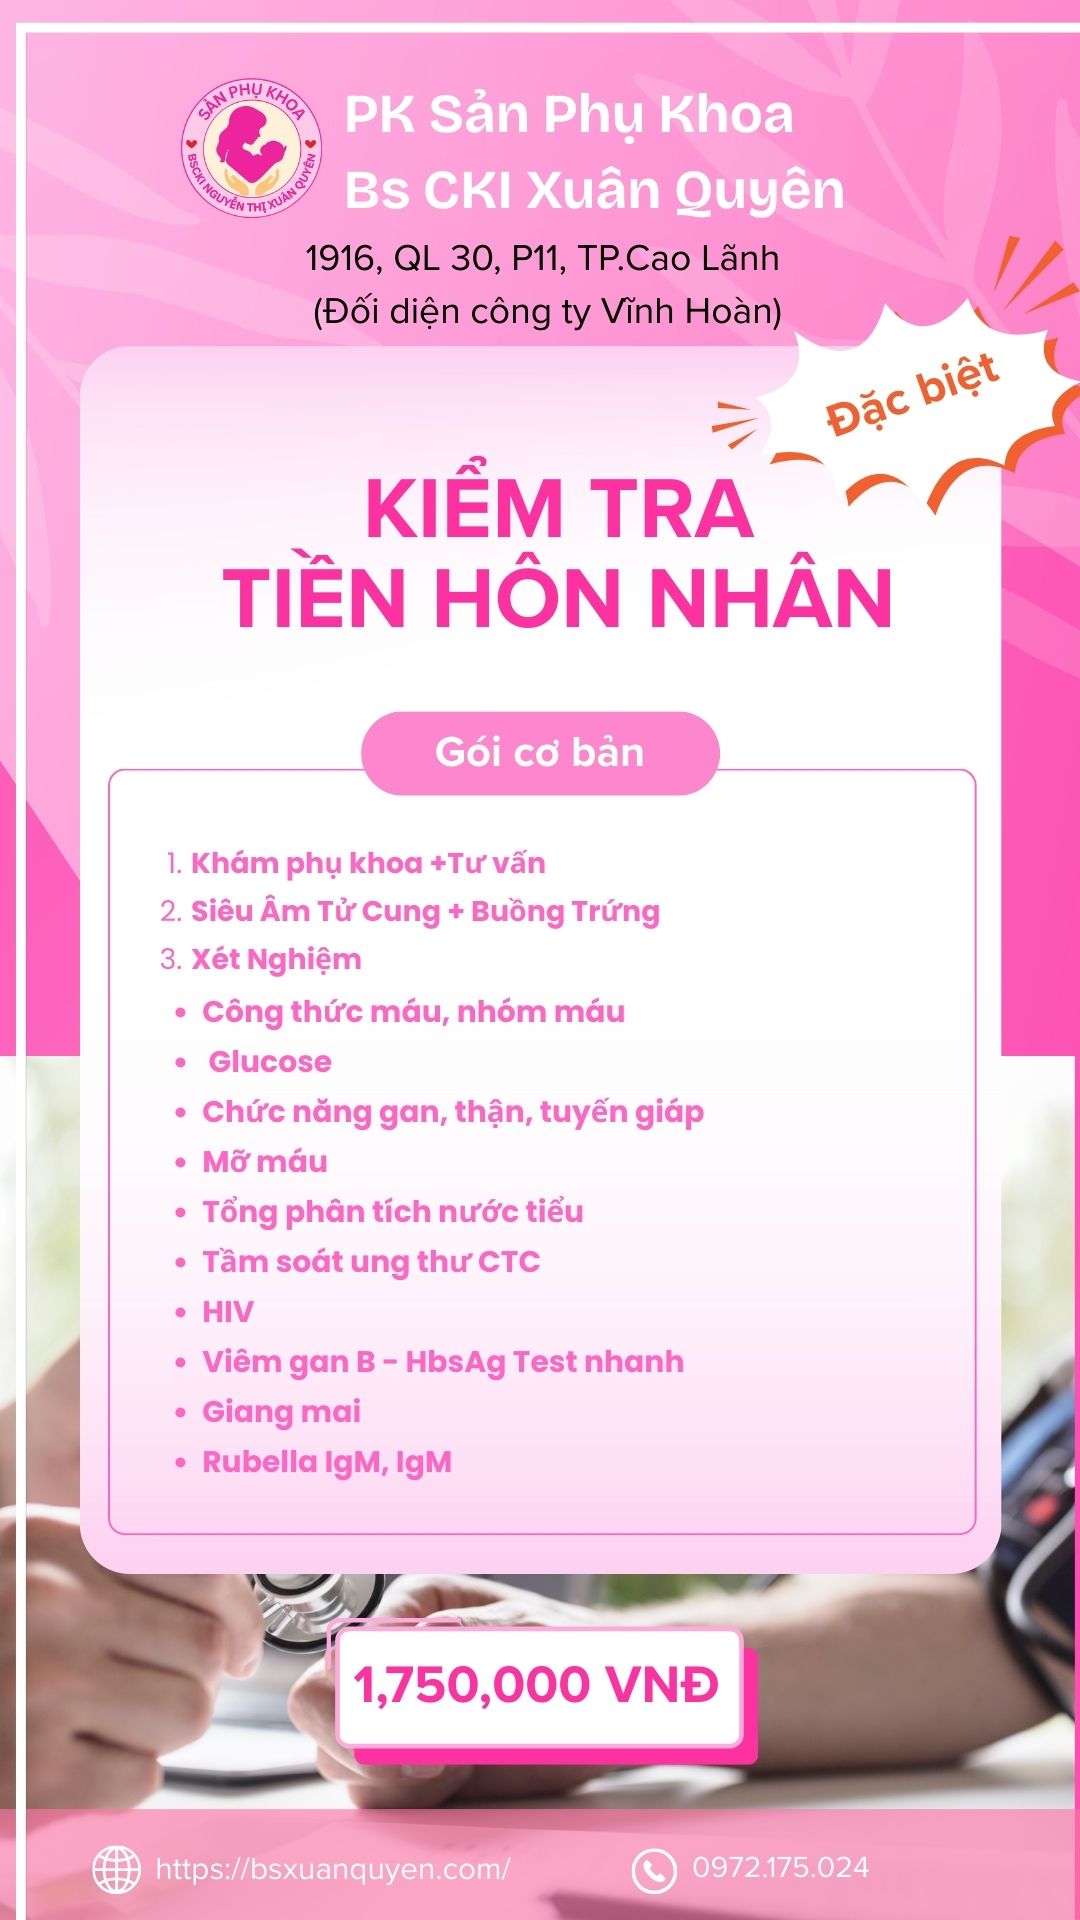

Bảng Giá tham khảo

Gói dịch vụ

Gói kiểm tra tiền hôn nhân nâng cao

gói kiểm tra tiền hôn nhân cơ bản